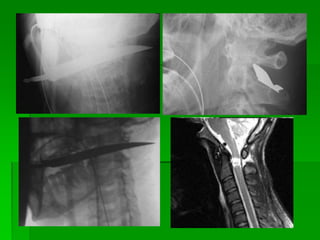

FRATURA DE PROCESSO ESPINHOSO C6

C7 T1 E TRUMA DE FACE COM FRATURAS

LE FORT 1

FRATURA DE PROCESSOESPINHOSO C6 C7 T1 E TRUMA DE FACE COM FRATURAS LE FORT 1